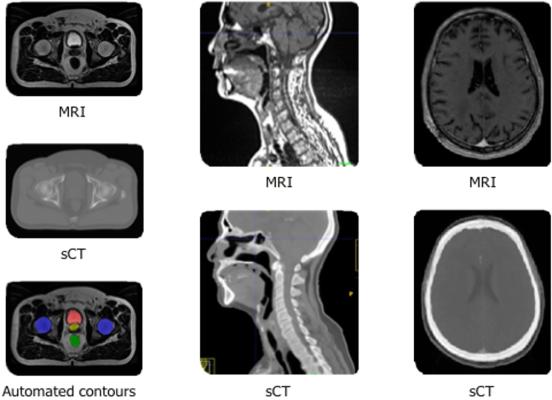

- Spectronic Medical Synthetic CT, MR[2] auto-segmentation: GE Healthcare will integrate Spectronic Medical AB’s AI-based software for more precise cancer treatment planning. This AI solution, in combination with GE Healthcare’s advanced AIR Recon DL technology, offers a deep learning solution and radiation therapy treatment planning alternative to standard CT images. The combined solution begins with GE Healthcare’s AIR Recon DL, a deep learning image reconstruction technology that leverages raw data from the MR scanner to reduce image noise, maximize image quality and resolution, and shorten scan times. The high-quality MR images generated by the GE scanner are then converted into synthetic CT images by Spectronic Medical’s AI-based solution, providing clinicians with the CT images they have come to expect with MR soft tissue details to more accurately target lesions and help improve patient outcomes. [3]